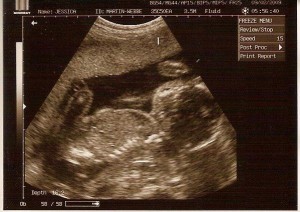

So why would I do an ultrasound if I have concern about their safety in pregnancy?  Aside from the fact that it’s only one ultrasound we plan on having during the entire pregnancy unless medically indicated otherwise, I have my reasons.  In my experience I have seen that a pregnant woman’s mind can greatly influence her pregnancy and her birth.  We have not had ultrasounds with each of our babies, with two we felt there was no medical reason to do so.  But then we discovered something: I struggled more with depression and feeling connected to my baby both during and immediately following the pregnancy when we didn’t find out than when we did.  There comes a point where I need something to help me start knowing the person I’m growing and connecting with them more than I’m connected to my IVs.  Knowing the sex of the individual growing inside of me is like a surge of power between me and my baby, energizing my connection and helping me get excited about having them.  That excitement helps make managing my HG this small challenge along the journey of getting this person.  The tiny potential risk of one ultrasound that gives us that connection as well as the peace of mind that the medications I’m on aren’t causing my baby to grow a second head means lower stress levels, higher endorphins, and begins the emotional journey from “I’m sick” to “we’re having a baby!”

With each of my pregnancies I find I worry more that something is wrong with my baby.  I used to think it was that I know more but now I think it’s not that complex.  We’ve had 5 healthy babies (Smunchie does have a minor heart defect and it was difficult and scary for a few months) and I start thinking there’s no way we’re going to have a 6th healthy baby.  Each time I imagine something worse.  Silly?  Probably.  Very real to me?  Yep.  And so, to help me sleep and to lower my anxiety, silly though it may be, we get the scan.  What if we do have a baby that is going to have special needs?  Well, things will proceed as already planned and we’ll start learning about navigating the world of parenting a child with special needs.  That’s not the problem for me, it’s the not knowing and the imagining that is.  Boy, girl, perfectly healthy, or special needs, this baby is ours and we love it very much, none of that’s going to change.